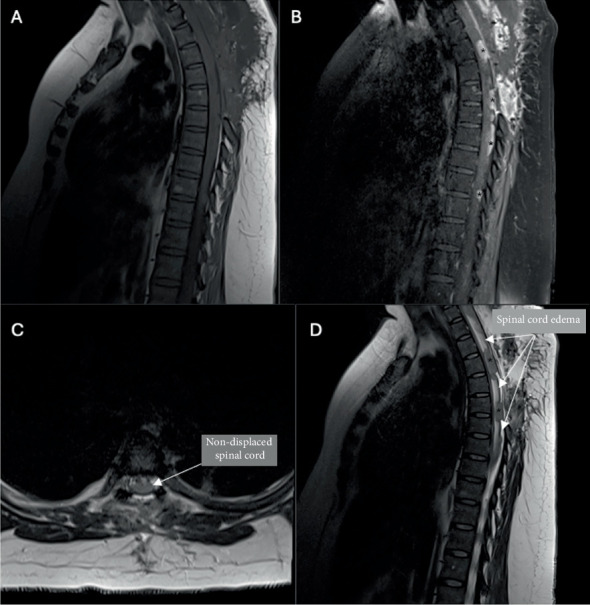

髓母细胞瘤是后颅窝的肿瘤,有沿脊髓发展为轻脑膜转移的倾向,通常称为“滴状转移”。髓母细胞瘤约占所有成人脑肿瘤的1%-2%,原发性脑脊膜髓母细胞瘤的报道非常有限。在此,我们提出一个罕见的病例,34岁的女性诊断为多灶性原发性脊髓轻脑膜髓母细胞瘤,没有颅脑受累。

Medulloblastomas are tumors of the posterior fossa that have a propensity to develop leptomeningeal metastases along the spinal cord, commonly known as "drop metastases." Medulloblastoma accounts for approximately 1%-2% of all adult brain tumors, and reports of primary leptomeningeal medulloblastoma are extremely limited. Herein, we present a rare case of a 34-year-old woman diagnosed with multifocal primary spinal leptomeningeal medulloblastoma without cranial involvement.